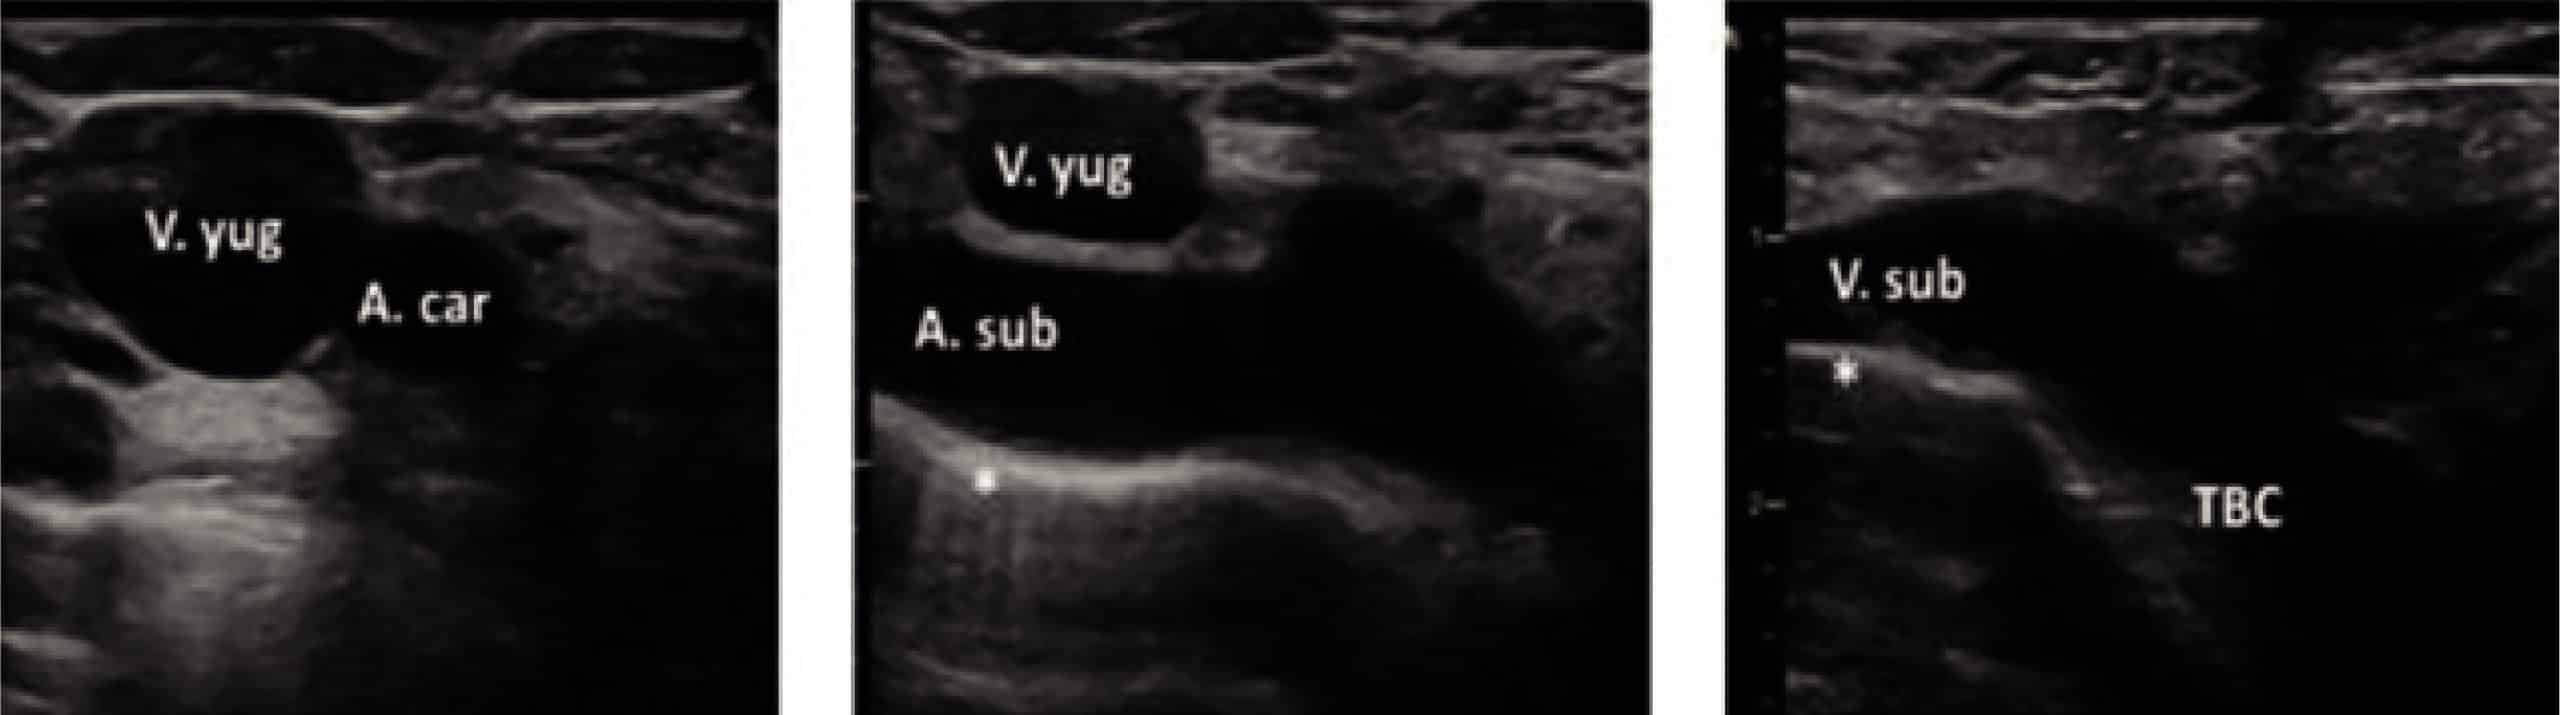

En cuanto a la vena braquiocefálica, el uso del ecógrafo permite una excelente vista longitudinal de la unión del VYI y VSC para identificar la vena braquiocefálica (VBC) en la región supraclavicular y sin ningún tipo de sombra causada por las estructuras óseas. El abordaje en plano (recomendado por los expertos) ofrece una buena visión tanto de la aguja como de la vena.

Tanto la vena subclavia como la braquiocefálica se visualizan mejor en plano longitudinal. Para ello lo que haremos es:

- Con una sonda lineal (modo 2D), el operador en el lateral de la cama -si vamos a canalizar lado izquierdo- o en la cabecera -lado derecho- y el paciente con la cabeza en una posición igual a la descrita para el acceso yugular; y los brazos rectos pegados al cuerpo (puede aplicarse leve tracción si se necesita incrementar el espacio); iniciaremos la exploración desde la vena yugular en posición trasversal.

- Una vez localizada la yugular iremos descendiendo la sonda hasta llegar a la fosa supraclavicular. En esta posición, visionando la arteria subclavia, se realiza un movimiento de basculación anterior con la sonda, dejándola prácticamente paralela a la clavícula, lo que nos permitirá ver tanto vena subclavia como el inicio del tronco braquiocefálico. En función de si nos desplazamos lateralmente hacia el exterior (vena subclavia) o hacia medial (tronco braquiocefálico) apreciaremos más uno vaso u otro.

Si nos decantamos por este abordaje, no olvidar tener localizada también la pleura para evitar realizar un neumotórax por yatrogenia. Además, en el caso de optar por la vena braquiocefálica izquierda deberemos de ver el arco aórtico antes de comenzar el procedimiento.